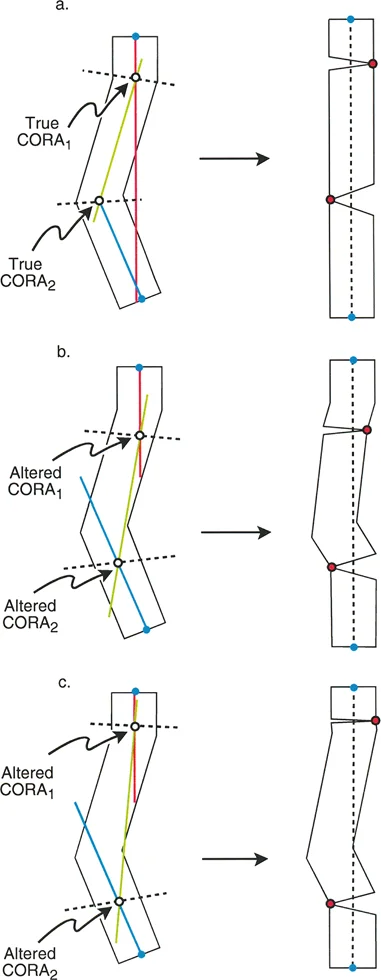

مستوى قطع العظم (Osteotomy Level)

مستوى قطع العظم (الشق الجراحي) يقع بالكامل تحت سيطرة الجراح. تحدد العلاقة الهندسية بين مستوى قطع العظم، وACA، وCORA النوع الدقيق للتصحيح الناتج، وتحدد ما إذا كان سيحدث تشوه ثانوي غير مقصود (مثل الانزياح غير المرغوب فيه).

إن فهم العلاقة المكانية بين القطع، والمفصلة، وقمة التشوه هو سر التصحيح الخالي من العيوب. تحدد قواعد بالي لقطع العظم النتائج الميكانيكية لخطتك الجراحية:

القاعدة الذهبية الأولى: القطع والمفصلة عند مركز الانحراف

عندما يمر كل من قطع العظم وACA مباشرة عبر CORA، يتم تصحيح التشوه الزاوي بشكل مثالي. يتم استعادة المحور الميكانيكي، ولا يوجد انحراف في المحور الميكانيكي (MAD)، وتبقى أجزاء العظم القريبة والبعيدة متوازية تمامًا. هذا هو السيناريو المثالي، والذي غالبًا ما يتحقق بقطع عظم وتدي بسيط (فتح أو إغلاق) عند قمة التشوه.

القاعدة الذهبية الثانية: المفصلة عند مركز الانحراف والقطع بمستوى مختلف

في بعض الأحيان، قد يكون قطع العظم مباشرة عند CORA غير ممكن سريريًا بسبب سوء حالة الجلد، أو وجود أدوات جراحية سابقة، أو مشاكل في جودة العظم في منطقة الكردوس/الجذع. إذا بقي ACA عند CORA، ولكن تم إجراء قطع العظم عند مستوى مختلف (أقرب أو أبعد عن CORA)، فسيتم تصحيح التشوه الزاوي بالكامل. ومع ذلك، ستنزاح نهايات العظم عند موقع قطع العظم بالنسبة لبعضها البعض.

* النتيجة السريرية: يؤدي هذا إلى "نتوء" أو تعرج في المحور التشريحي، لكن المحور الميكانيكي العام وتوجيه المفصل يظلان متوائمين تمامًا.